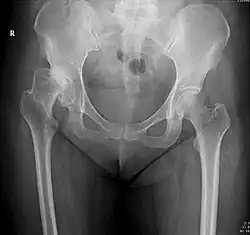

Subluxation de la hanche

La subluxation de la hanche est la perte de contact, partielle et permanente, entre les deux surfaces articulaires que sont la tête fémorale et le cotyle.

Dans le langage médical, une luxation désigne un déplacement d'une surface articulaire par rapport à une autre. Il y a alors une rupture de continuité articulaire, comme si l'articulation se déboitait. Dans le cas d'une subluxation, la perte de contact n'est pas totale. Très douloureuse, la subluxation acquise de la hanche occasionne une impotence partielle voir complète du membre touché soit des difficultés voire une impossibilité à se servir de l'articulation de la hanche.

La subluxation est principalement la conséquence d'une malformation de la hanche congénitale dite dysplasie de la hanche ou de façon plus moderne dysplasie développementale de la hanche[1]. Elle est plus rarement la séquelle d'une luxation mal traitée. Elle peut aussi être la conséquence évolutive d'une infirmité motrice cérébrale avec tétraplégie[2].